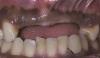

Внутриротовые параметры: в первом квадранте – несъемный металлокерамический мостовидный протез 13/12/11 зубов, консольный протез на месте 14/15/16 зубов с опорой на имплантат, диастема между 14 и 13 зубами.